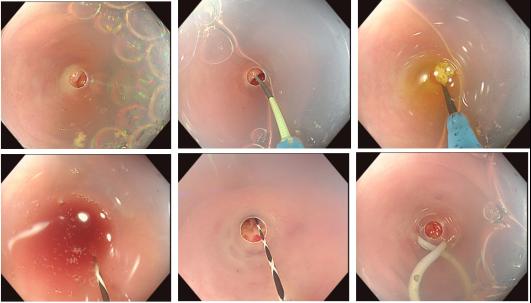

消化内科编制床位141张,年门诊平均就诊量约十万余人次,出院约6000余人次,内镜诊疗60000余人次,手术或治疗4千余例。我院地处川东北地区,长期收治不明原因腹水、不明原因消化道出血、不明原因腹痛、急性重症胰腺炎、肝硬化伴严重并发症及消化道大出血等疑难危急重症病人。作为川东北地区消化系统内科治疗的标杆,消化内科一直致力于示范和推广高水准的消化道诊疗技术,为提高诊疗技术,为广大患者提供更好的服务,我科购进了奥林巴斯小探头超声内镜、纵轴线阵扫描超声胃镜、奥林巴斯290色素放大内镜(NBI)、十二指肠镜、富士7000放大内镜、富士双气囊小肠镜等内镜下诊疗的高端设备。消化内科极其重视消化道肿瘤的早诊早治及消化内镜下一系列医疗技术,开展了EMR、 ESD、STER、POEM、EUS及内镜下止血等手术。同时,还大力开展消化放射介入治疗如ERCP等多项介入技术。消化内科联合急诊医学科、介入科、普外科等多科建立危险性消化道出血 MDT 团队,建立“危险性上消化道出血救治区域中心”,7×24 小时绿色通道,提供全面、优质诊疗方案,缩短危险性消化道出血急诊救治时间,大大提高了患者生存率。在临床工作中努力深化亚专科和各专业组建设,各专业组通过进修学习及各类学术交流、病例研讨等活动,不断提升团队整体实力,为患者提供更精准、更专业的医疗服务,努力在医学亚专业领域内实现新的突破与飞跃。

STER治疗食管固有肌层肿瘤